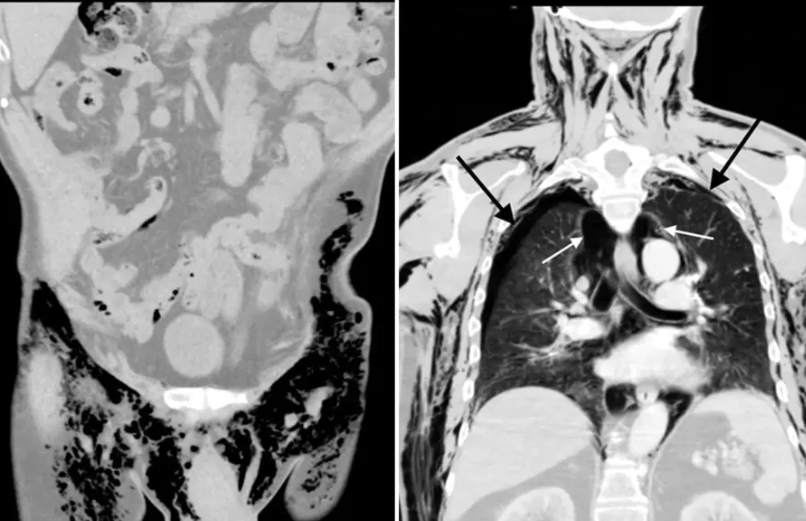

Una radiografia del torace dell’uomo ha rivelato che l’aria si era accumulata tra i polmoni e la parete toracica (pneumotorace bilaterale), l’aria occupava la parte centrale del torace (pneumomediastino) e l’enfisema sottocutaneo era presente nell’addome, nel perineo e nello scroto. I medici hanno anche osservato che una ferita aperta sullo scroto, causata da un intervento chirurgico ai testicoli cinque mesi prima, stava rilasciando aria.